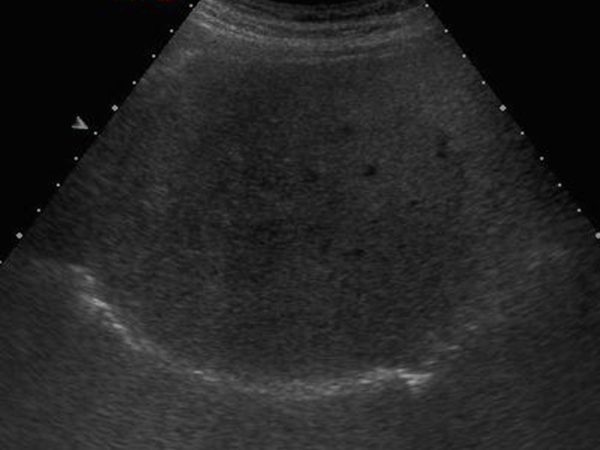

Sán lá gan

» Thông tin: Nam giới – 52 tuổi.

» Lâm sàng: Kiểm tra sức khỏe.